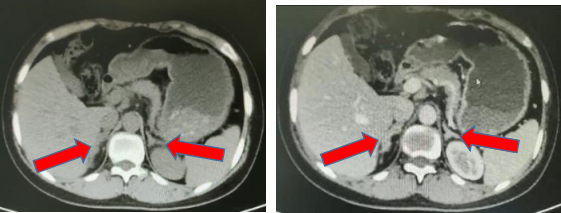

入院后通过相关检查发现小周血钾低,醛固酮和肾素的比值升高,雌二醇、睾酮等性激素降低,皮质醇也比正常人低,生长激素是正常的,骨密度减少,肾上腺CT发现双侧肾上腺增生。

图1 肾上腺CT平扫及增强影像

经科室仔细分析病史、临床表现、辅助检查,考虑小周的疾病可能是一种罕见病叫先天性肾上腺皮质增生症(17α-羟化酶缺乏症),引起先天性肾上腺皮质增生症,导致小周一直没来月经,并出现高血压、低血钾、手足畸形、外阴及**不发育等一系列的症状。